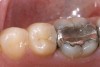

Replacement of existing restorations is responsible for 75% of all operative dentistry.15,19 The reasons for placement and replacement of restorations of direct restorative materials include: primary caries (Figure 1 and Figure 2); recurrent caries (Figure 3); poor margins (Figure 4 and Figure 5); restoration fracture (Figure 6 and Figure 7); tooth fracture (Figure 8); esthetics (Figure 9); non-carious tooth structure lost (attrition, abrasion, abfraction, erosion) (Figure 10); and pain/sensitivity.

Fig. 5 Defective margins. Mandibular second molar with a Class II composite resin with a defective facial–gingival margin.

Figure 5  Defective margins. Mandibular second molar with a Class II composite resin with a defective facial–gingival margin.

Figure 5